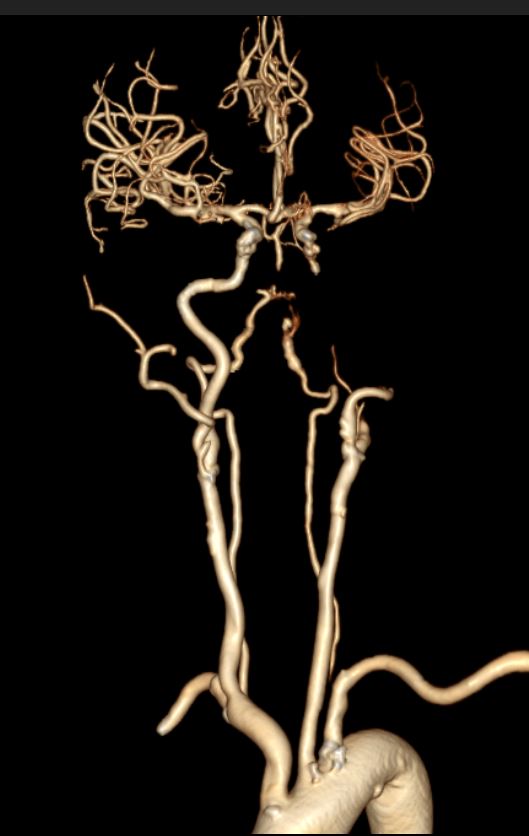

进一步完善头颈部CTA检查,提示左侧颈内动脉闭塞。

虽CTA提示颅内段颈内动脉及左侧颈内动脉颅内分支无明显缺失,但大脑中动脉远端分支明显稀疏,显影不佳。再结合头颅磁共振了解代谢情况。

结合既往患者脑梗死行头颈部血管CTA提示双侧颈内动脉C4段重度狭窄,考虑此次发病左侧重度狭窄急性闭塞可能,对侧颈内动脉代偿不充分,和家属沟通,家属态度积极,理解病情,遂急诊手术治疗。